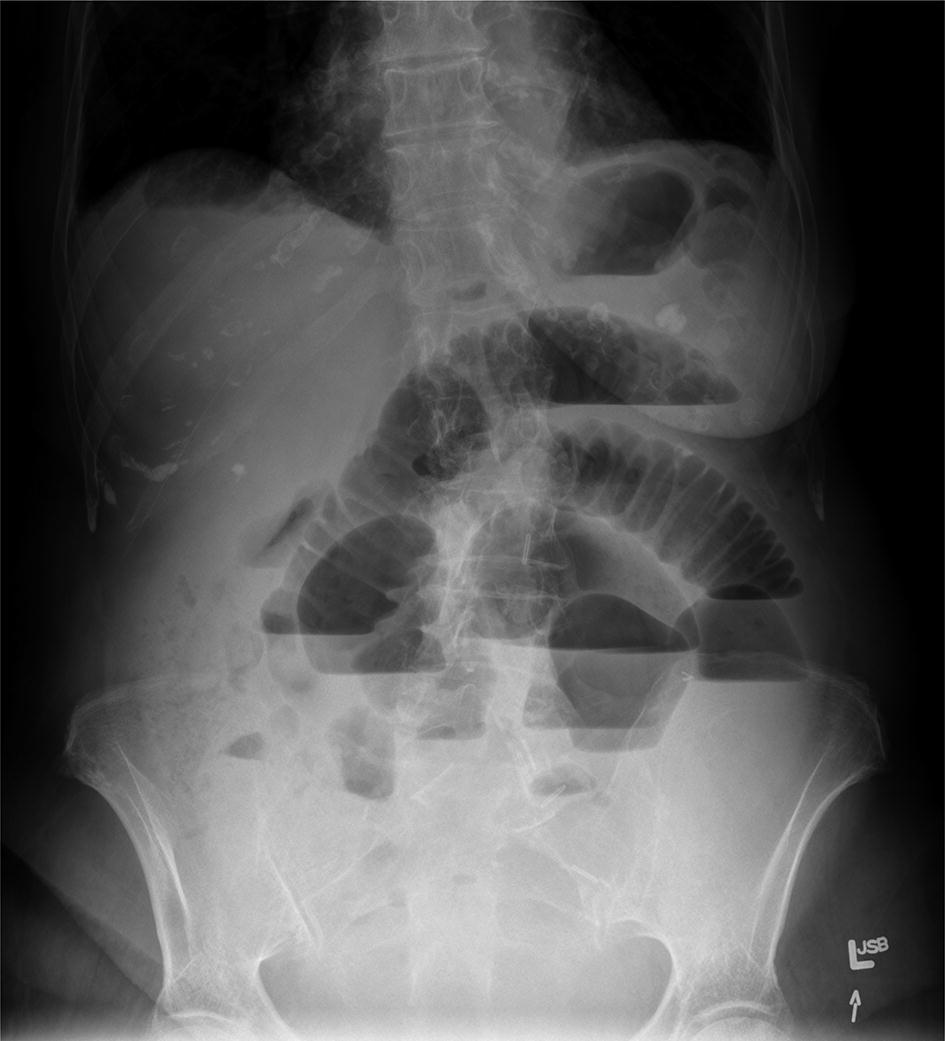

But as you can see from the images above you cannot reliably look for air under the diaphragm in an AXR and thus a CXR is. Typical abdominal X-ray features of small bowel obstruction include dilation of the small bowel 3cm diameter and much more prominent valvulae conniventes creating a coiled-spring appearance. Adhesions are the most common cause of small bowel obstruction in the developed world accounting for 75 of all cases. It integrated radiological images including X-ray computed tomography and magnetic resonance imaging plus clinical correlations and self-evaluation. Whether x-ray is supine or erect for fluid and gas levels correct orientation RightLeft Location of bowel small central large peripheral. A US doctor answered Learn more.

Approach to AXR Bowel gas pattern Extraluminal air Soft tissue masses Calcifications 4. This tutorial will discuss these steps. X-rays of the belly may be done to check the area for causes of abdominal pain. Typical abdominal X-ray features of small bowel obstruction include dilation of the small bowel 3cm diameter and much more prominent valvulae conniventes creating a coiled-spring appearance. Abdominal X-Ray - Small bowel obstruction - Small bowel obstruction can be identified by the dilated loops of centrally placed bowel with the venae commitantes circular bands of muscle that span the entire width of the bowel.

Because of the difference in X-ray absorption by air and soft tissues the intestinal structures intestinal air can be differentiated from their surroundings. A system for reporting an abdominal X-Ray. X-rays of the belly may be done to check the area for causes of abdominal pain. 2 Air in the abdomen Air rises to the top when there is pneumoperitoneum eg. Abdominal X-Rays Tutorial EKhalili Pouya 2018.